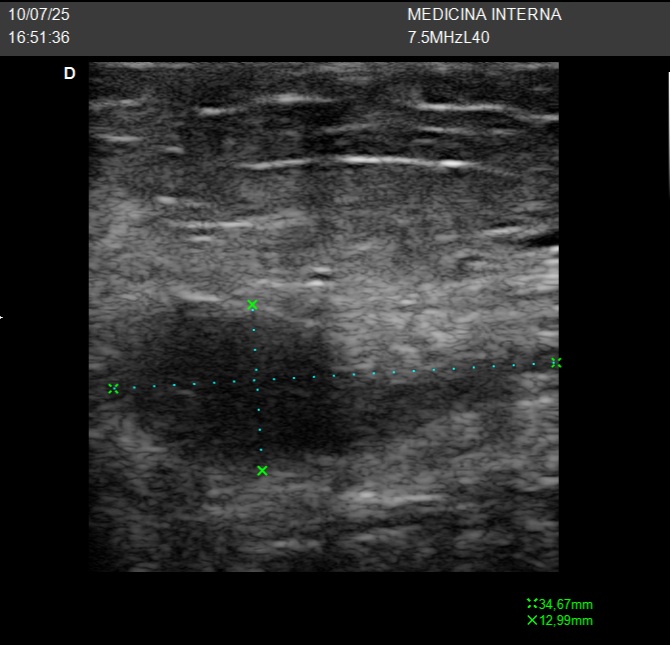

Una paciente joven acude preocupada por un pequeño bulto que notó hace un par de días en la parte baja del abdomen. Al explorarlo no dolía, pero se palpaba firme, bien delimitado. ¿Podría ser un ganglio? ¿Un quiste?

La ecografía mostró un quiste epidérmico superficial, bien delimitado, sin signos inflamatorios. Bastó una imagen rápida para tranquilizar a la paciente y evitar pruebas innecesarias.

Recordar por pequeño que es el bulto, debemos palpar bien, para colocar la sonde lineal correctamente, y ajustar los parametros de profundidiad muy superfecial, con la frecuencia al maximo, con centrar el foco y la gancncia. Una vez en el foco adecuado hacer los zum necesarios.